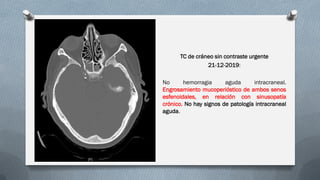

TC de cráneo sin contraste urgente

21-12-2019:

No hemorragia aguda intracraneal.

Engrosamiento mucoperióstico de ambos senos

esfenoidales, en relación con sinusopatía

crónico. No hay signos de patología intracraneal

aguda.